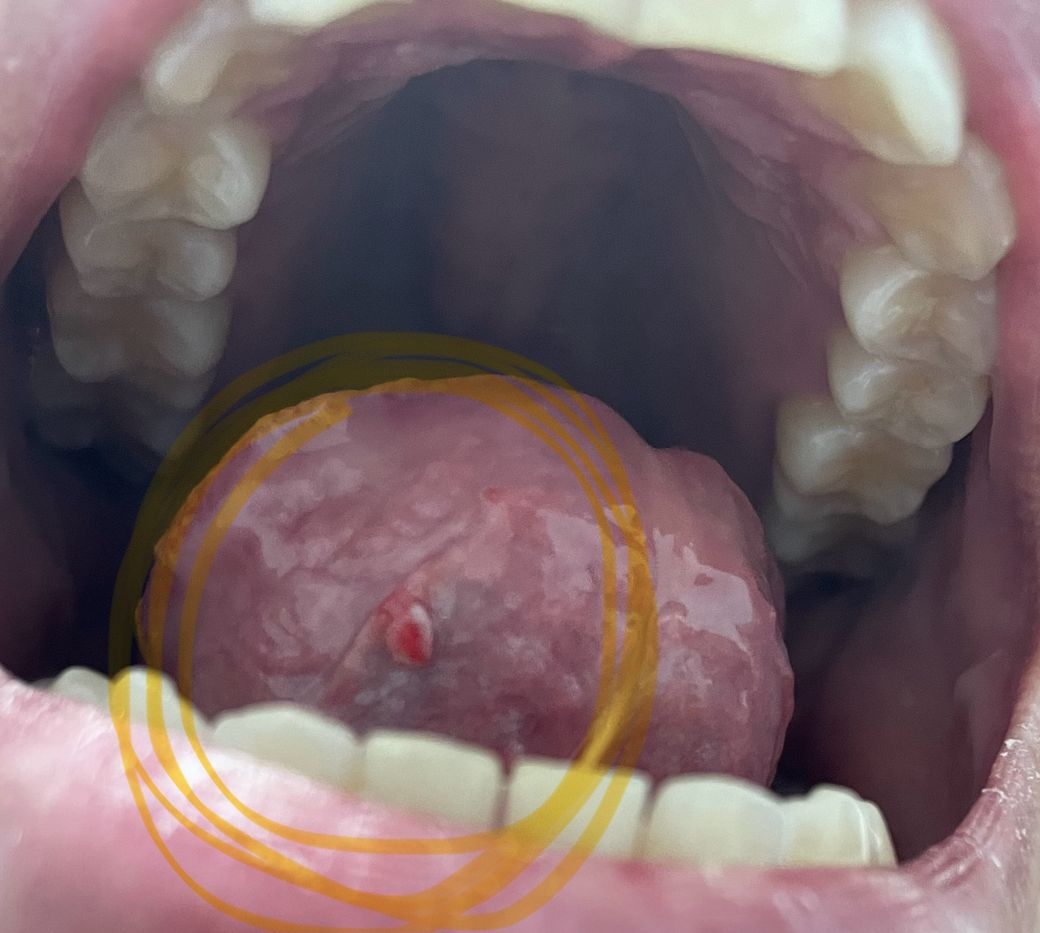

혀 밑에 돌기같은게 생겼는데 달랑거리고 움직여요

혀 밑에 동그란 무언가가

달랑달랑 거려요

얼마전까진 이런게 없었는데 뭐죠?

약간 입병난 느낌이 나서 입안을

봤더니 이러네요

심각한 건가요??

섬유종과 같은 양성 종양이 아닐까 의심스럽지만 전문 진료과목이 아니라 불확실합니다. 이비인후과를 방문해보시는 것이 좋겠습니다.